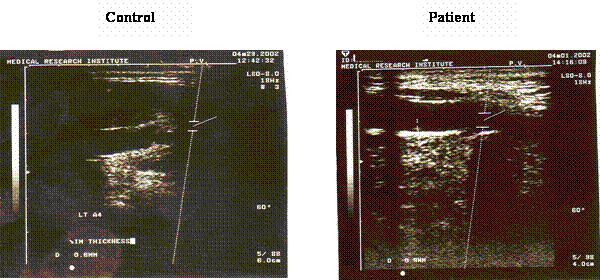

Figure 4 shows the result of the carotid ultrasonography in a patient with coronary heat disease and a young control subject. There was an apparent thickness of the carotid intima in the patient ultrasonography when compared with the control. Furthermore, there was a weak positive correlation between the CIT and the tHcy level, the correlation coefficient was 0.34.

Figure 4

Ultrasonography for the carotid artery in a control subject and a patient with coronary heart disease. Carotid ultrasonography for measurement of the carotid artery intimal thickness (CIT) was done using the ultrasonic machine equipped with high frequency linear array transducer. The examination was done for the right and left common carotid arteries and the mean values of the two sites were used in the analysis. There is an apparent increase in the degree of carotid intimal thickness in the examined patient (0.9mm) compared with 0.6 mm in the control subject.